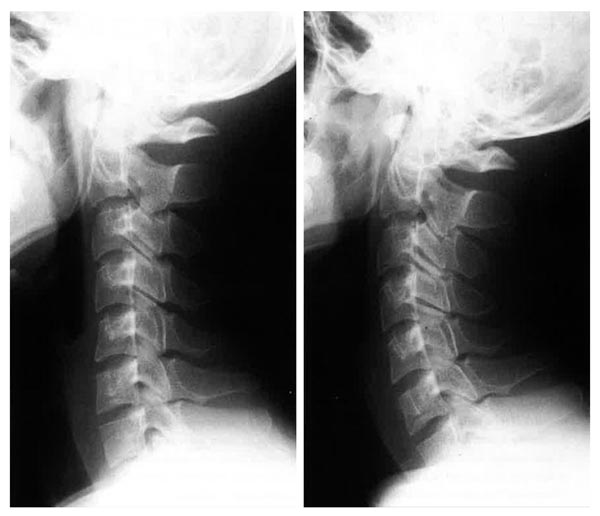

治療後(右)は治療前(左)に比べて首のカーブが復活(提供写真)